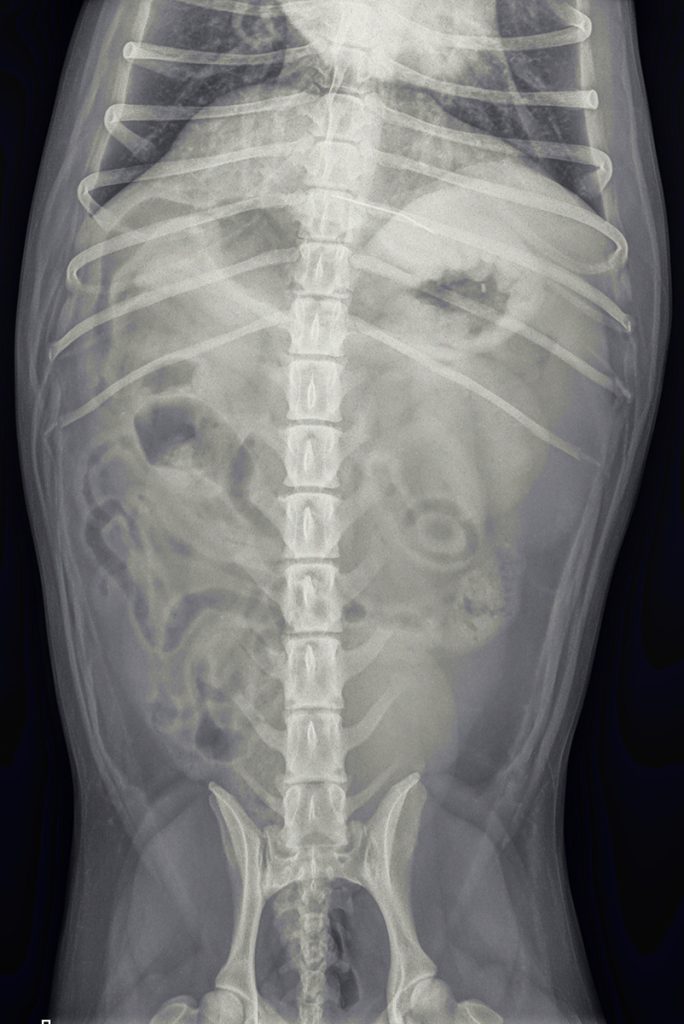

Een paar dagen later is het zo ver. We maken voor de zekerheid opnieuw foto’s, om de juiste lokatie te controleren. De naald lijkt aardig op dezelfde plek te liggen.